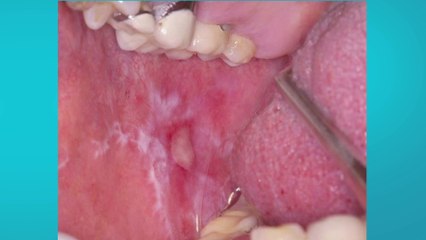

Dentro del contexto del Día Mundial de la Prevención del Cáncer de Cuello Uterino, celebrado cada 26 de marzo, el ISSSTE, liderado por el director general Martí Batres Guadarrama, reafirma su dedicación a prevenir y luchar contra este mal.